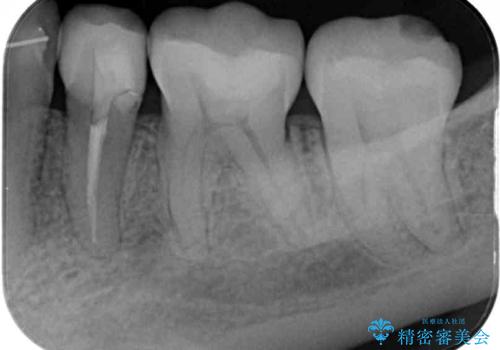

矯正の後戻りの改善と銀歯をセラミックに

矯正治療後には、下顎臼歯の目立つ銀歯をセラミックインレーにて修復治療を行いました。

軽微な後戻りの治療であったため、十分に治療を行うことができました。

口を開けたときに金属が見えなくなり、患者様には大変満足していただきました。